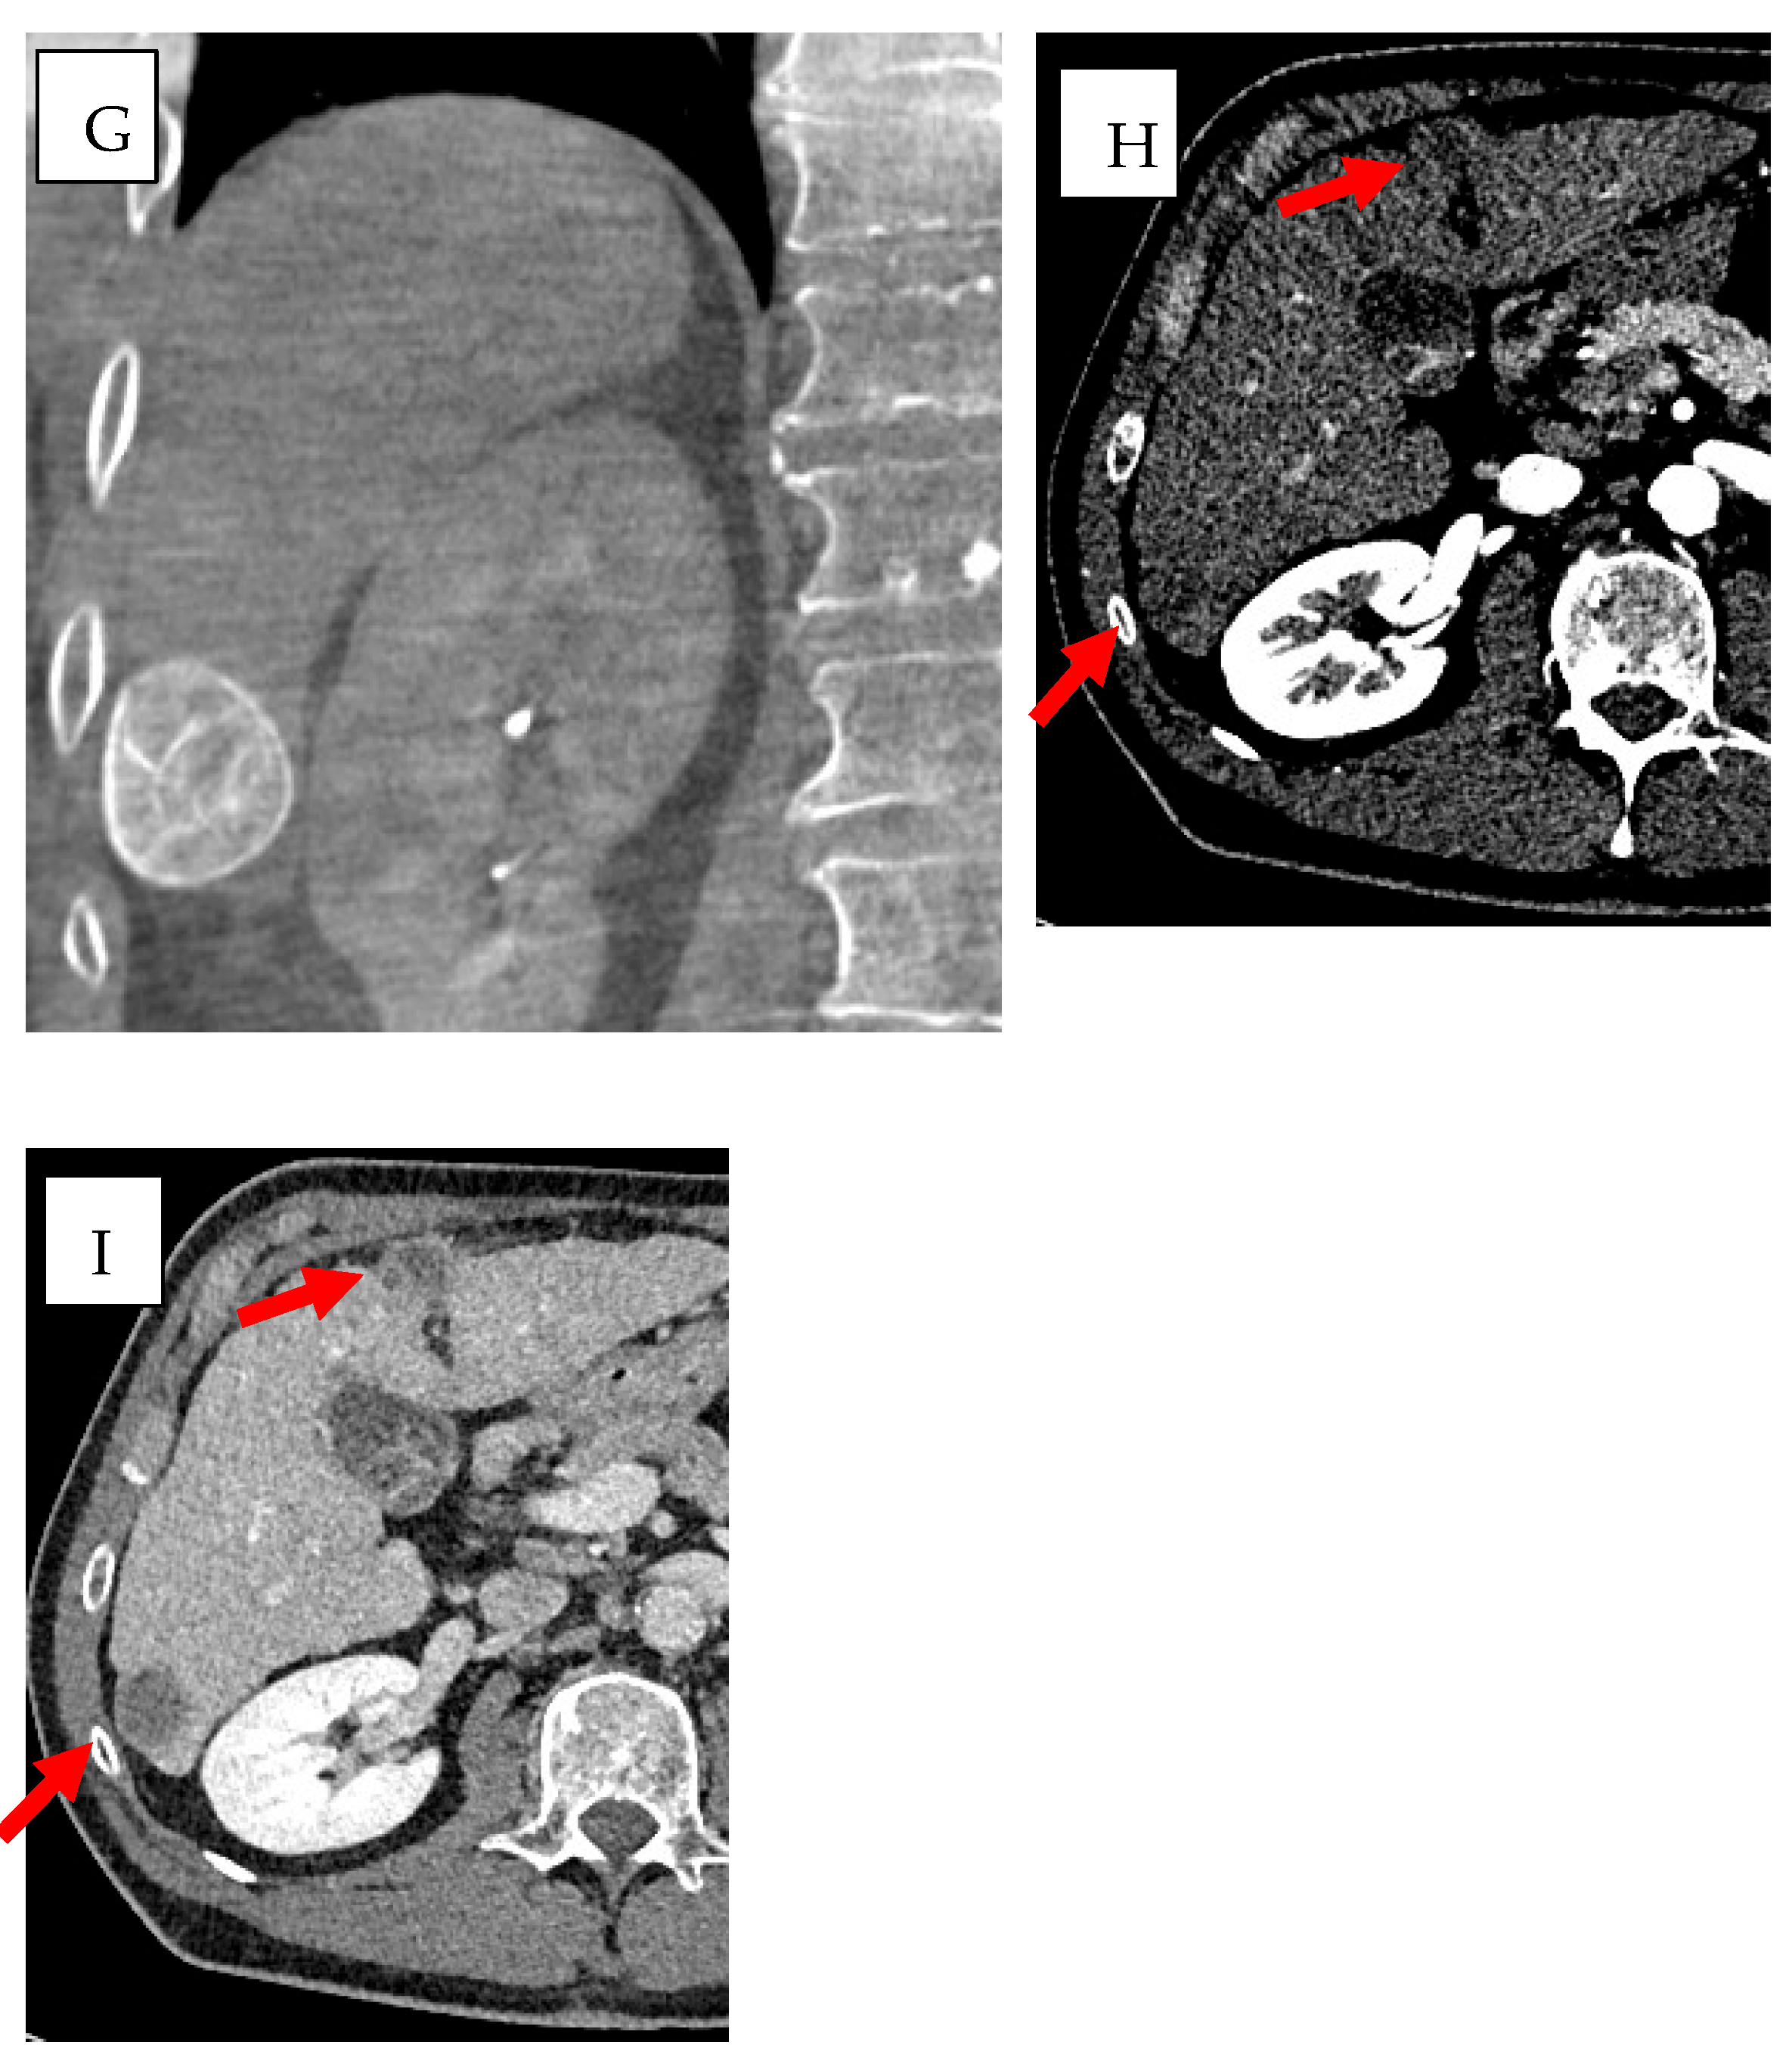

- Biondetti, P.; Ierardi, A.M.; Casiraghi, E.; Caruso, A.; Grillo, P.; Carriero, S.; Lanza, C.; Angileri, S.A.; Sangiovanni, A.; Iavarone, M.; et al. Clinical Impact of a Protocol Involving Cone-Beam CT (CBCT), Fusion Imaging and Ablation Volume Prediction in Percutaneous Image-Guided Microwave Ablation in Patients with Hepatocellular Carcinoma Unsuitable for Standard Ultrasound (US) Guidance. J. Clin. Med. 2023, 12, 7598. [Google Scholar] [CrossRef]